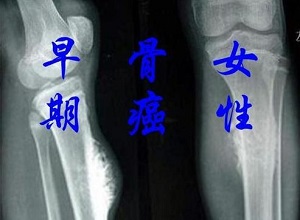

郑州肿瘤医馆排名:骨癌早期身体会有什么症状?骨癌是一种恶性骨肿瘤,其早期症状包括局部骨肿块.疼痛.功能障碍,如果肿瘤体积较大,可导致相应部位出现压迫症状。1.局部骨肿块:即部分骨癌患者可接触局部固定肿块或局部肿胀,一常见的是关节肿胀,表现为关节附近红肿.发热等。2.疼痛:是本病早期一重要的症状。疾病...

郑州肿瘤科医馆:出现以下6种情况小心骨癌。“骨癌”,其发展迅速,预后不佳,死亡率高。恶性骨肿瘤分为原发性和继发性。从体内其他组织或器官的肿瘤经血液循环、淋巴系统转移至骨骼为继发性恶性骨肿瘤。因此,郑州御和堂中医师提醒:出现6种情况小心骨癌1、骨癌的早期症状有自发性骨折。2、在骨的表面可及一...